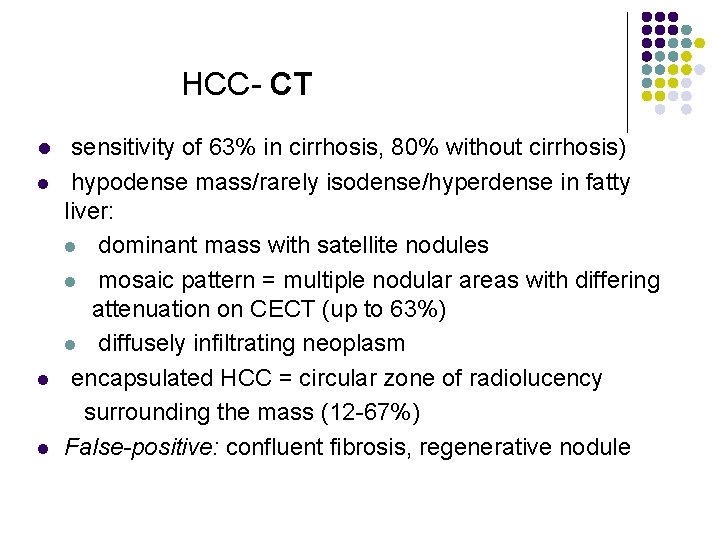

HCC- CT l l sensitivity of 63% in cirrhosis, 80% without cirrhosis) hypodense mass/rarely isodense/hyperdense in fatty liver: l dominant mass with satellite nodules l mosaic pattern = multiple nodular areas with differing attenuation on CECT (up to 63%) l diffusely infiltrating neoplasm encapsulated HCC = circular zone of radiolucency surrounding the mass (12 -67%) False-positive: confluent fibrosis, regenerative nodule